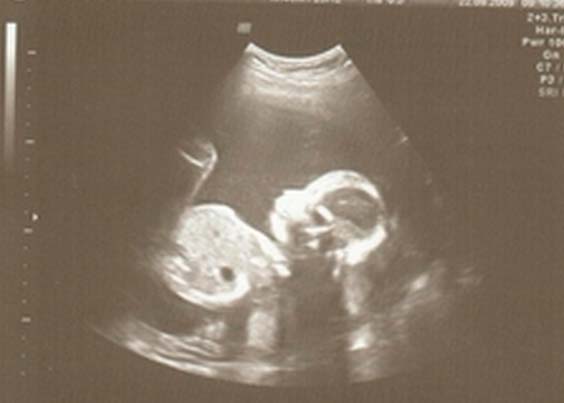

Foto de ultrassom na semana 22